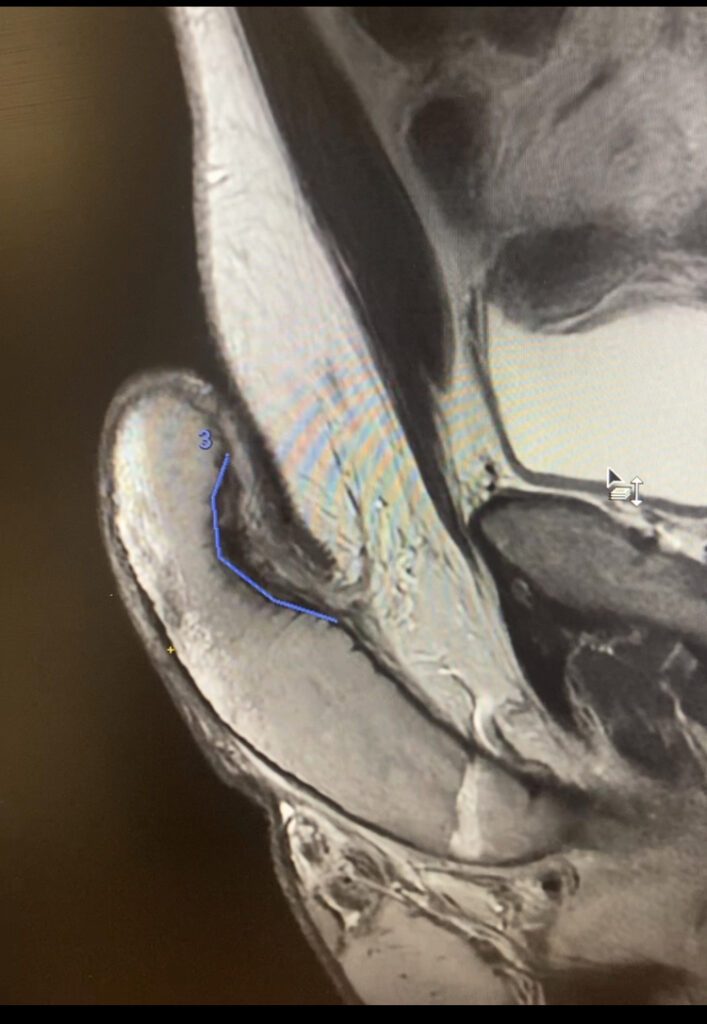

La maladie de Lapeyronie demeure encore trop souvent méconnue, alors qu’elle concerne un nombre significatif d’hommes et peut avoir un retentissement majeur sur la qualité de vie, la sexualité et le bien-être psychologique. Cette pathologie se caractérise par la formation de plaques fibreuses au niveau de l’albuginée, responsables de courbures péniennes, de douleurs et parfois de troubles de l’érection.

Au cœur de la prise en charge moderne de la maladie de Lapeyronie, l’imagerie joue un rôle central. Elle permet non seulement de confirmer le diagnostic, mais surtout de comprendre précisément la morphologie des plaques et leurs conséquences fonctionnelles, condition indispensable à une stratégie thérapeutique adaptée.

L’échographie pénienne, associée au Doppler, et dans certaines situations l’IRM réalisée sous pharmacostimulation, constituent des outils de référence. Ces examens dynamiques permettent :

• une cartographie précise des plaques de fibrose, qu’elles soient superficielles ou profondes,

• l’évaluation de leur activité inflammatoire et de leur retentissement hémodynamique sur la fonction érectile,

• et, in fine, une orientation thérapeutique ciblée, qu’il s’agisse d’un traitement localisé (injections intralésionnelles, ondes de choc, chirurgie conservatrice) ou d’un simple suivi évolutif.